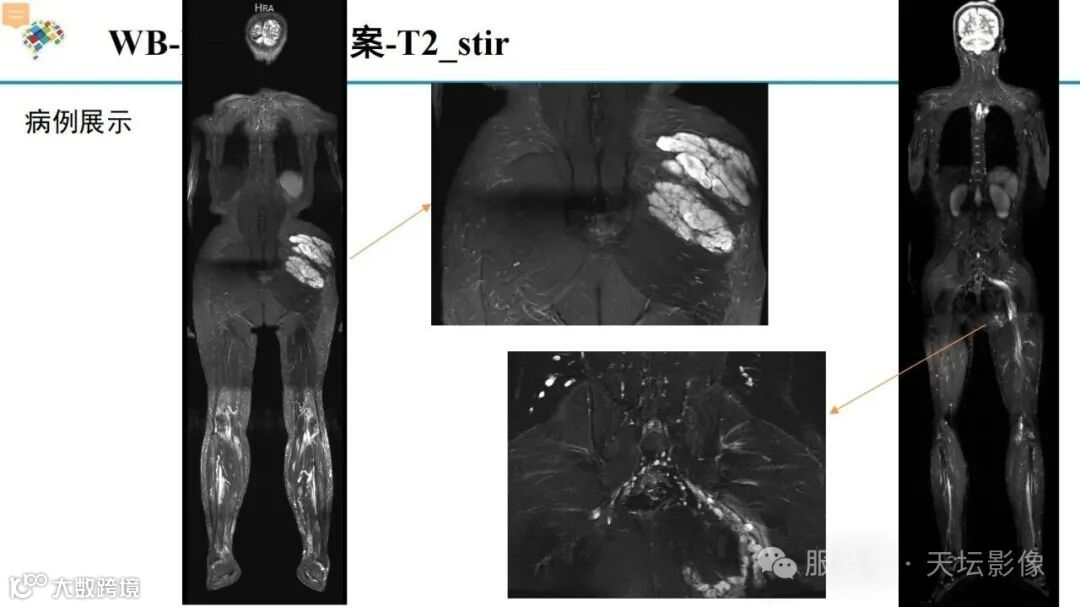

天坛扫描方案!NF1相关丛状神经纤维瘤推荐MR扫描方案